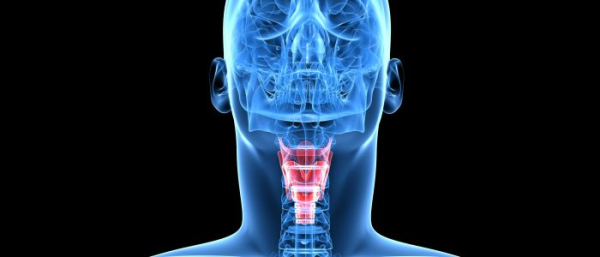

Неприятные ощущения во рту, при глотании пищи, охриплость голоса и кашель, могут свидетельствовать о развитии распространенного недуга — ангиомы гортани. Это заболевание относится к доброкачественным опухолям. Для болезни характерно медленное развитие, поэтому ангиому легко вылечить на начальных стадиях. Угрозы для жизни образование не несет, но обследование у отоларинголога обязательно.

Ангиома гортани может давать о себе знать дискомфортом при глотании, хриплым голосом и отличается медленным патогенезом.

Ангиома может поражать и деформировать в разной степени полость гортани и сосуды.